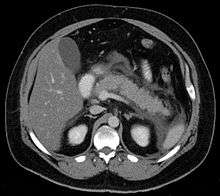

Calcified pancreatic duct stones with some free intraabdominal fluid

For imaging, abdominal ultrasound is convenient, simple, non-invasive, and inexpensive.[24] It is more sensitive and specific for pancreatitis from gallstones than other imaging modalities.[23] However, in 25–35% of patients the view of the pancreas can be obstructed by bowel gas making it difficult to evaluate.[22]

A contrast-enhanced CT scan is usually performed more than 48 hours after the onset of pain to evaluate for pancreatic necrosis and extrapancreatic fluid as well as predict the severity of the disease. CT scanning earlier can be falsely reassuring.